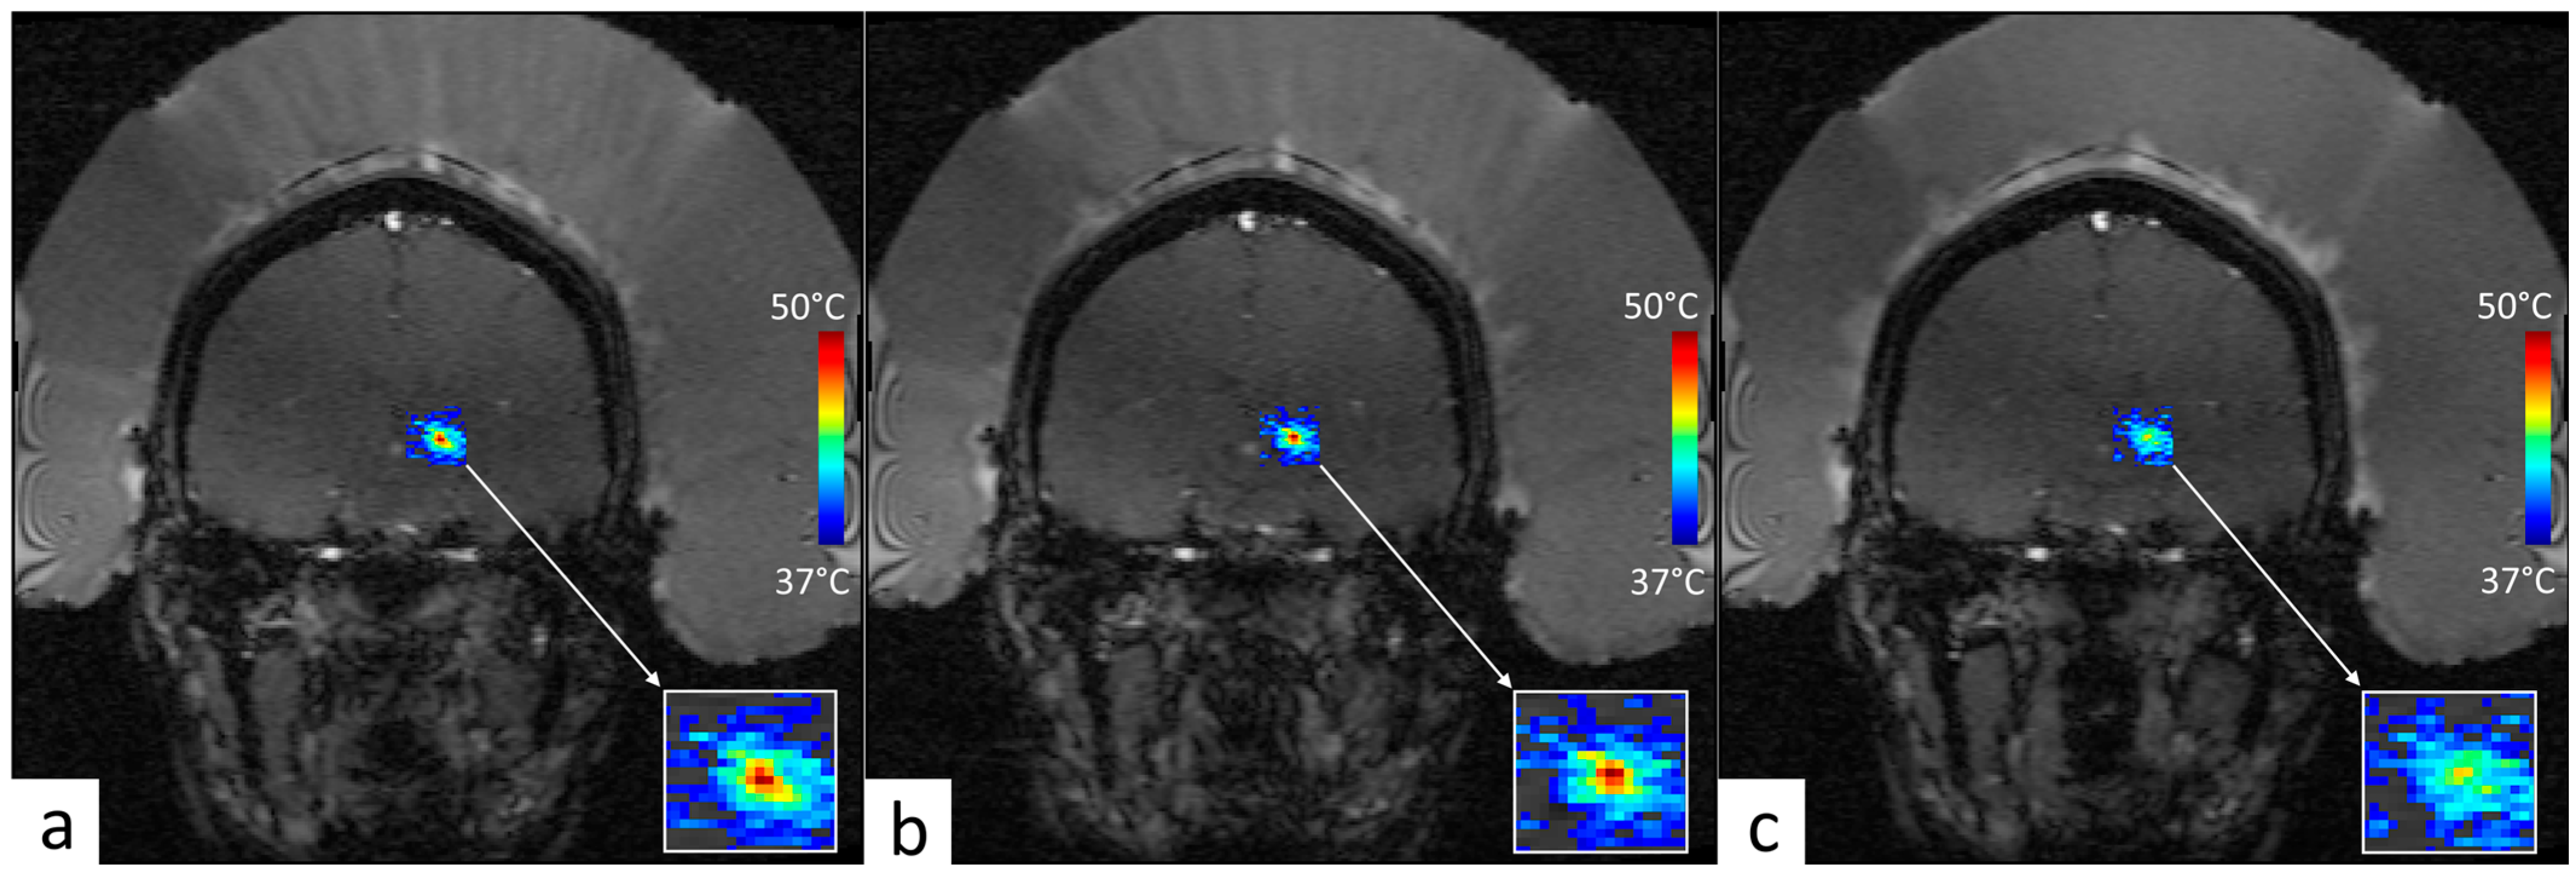

2.7. Retrospective Analysis of MRgFUS Thalamotomy Data

3.3. Retrospective Analysis of Clinical MRgFUS VIM–Thalamotomy Data